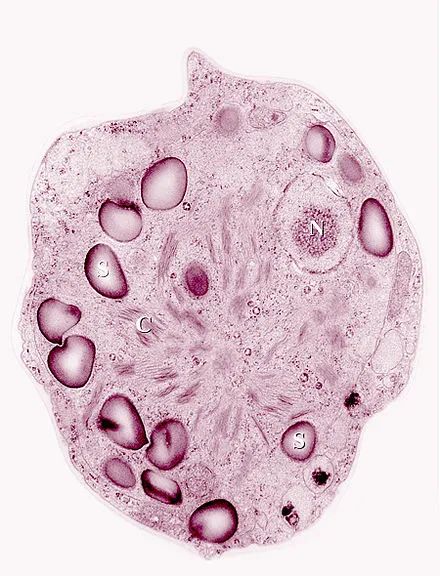

据相关专家分析,此次“西瓜雪”是白雪被一种名为“雪藻”的藻类中蕴含的类胡萝卜素“染色”的。

这种藻类多生长在较为寒冷地区,耐寒性极强,在低纬度的南极大陆沿海较为常见。

初生的雪藻呈绿色,为了抵御白雪反射的强烈紫外线,雪藻会产生类胡萝卜素等物质,使得生长过程中呈现出从绿色到红色的变化,这也就是我们看到的绿色雪和红色雪的原因。